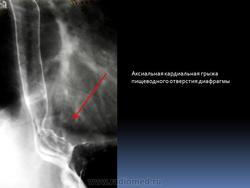

Рак пищевода.

Приложения:

1.rak_.4_133.jpg2.rak_.6_85.jpg